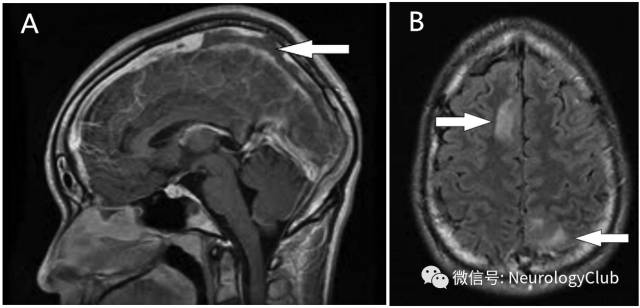

脑动静脉系统受累

(图25:A:可见上矢状窦后半部充盈缺损;B:右侧额叶和左侧顶叶高信号病灶)